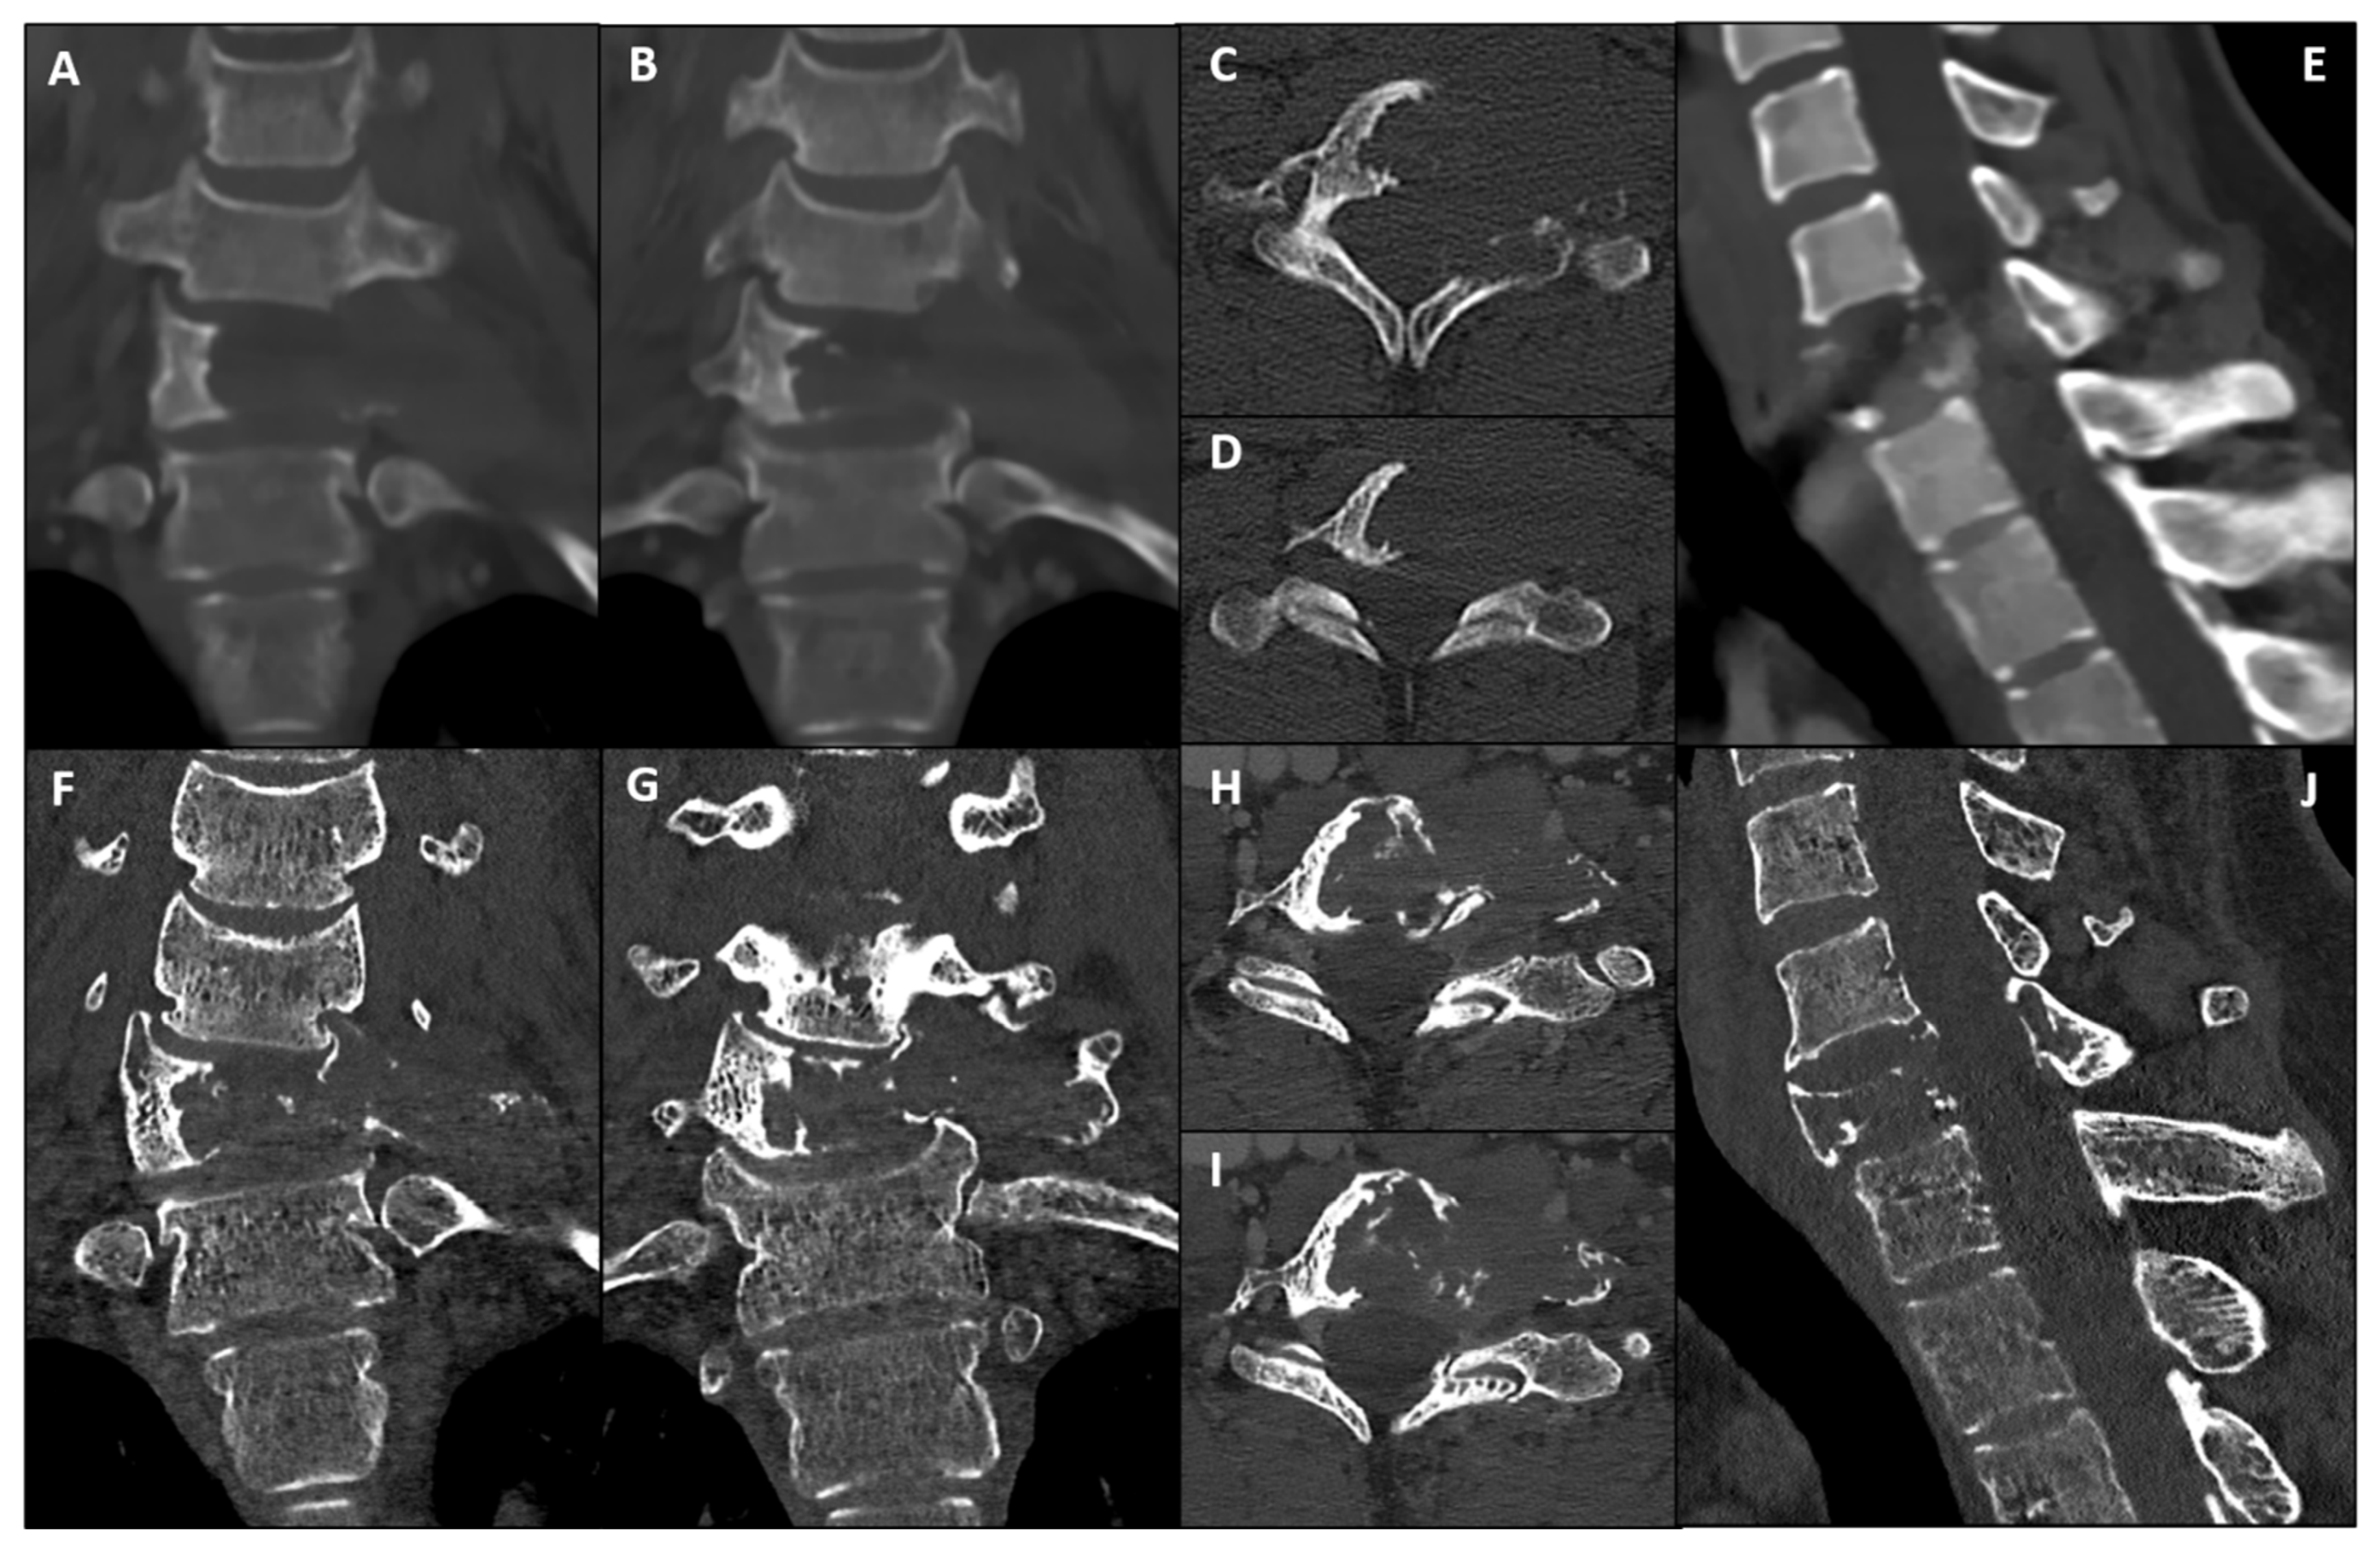

2. Case Presentation

3.1. Anterior Step: Corpectomy and VA Repair

4. Discussion

4.2. Robotic Planning Under Hardware Constraints: Approach, Safety, and Alternatives